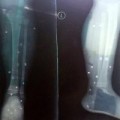

Nạn nhân được các bác sĩ phẫu thuật nối lại bàn tay trái bị chém đứt lìa.

BS Nguyễn Minh Trực, Phó Trưởng khoa Chấn thương chỉnh hình BV Đa khoa tỉnh Đắk Lắk, cho biết bệnh nhân Vũ Văn Hoàng được chuyển lên từ BV huyện Krông Ana trong tình trạng mất máu nhiều, mặt bị sưng, tay trái bị chém đứt. Bệnh nhân đã được phẫu thuật nối lại bàn tay và tiếp bốn đơn vị máu. Sau khi qua cơn nguy kịch, người nhà đã xin chuyển nạn nhân đến BV Chấn thương chỉnh hình TP.HCM để tiếp tục điều trị.